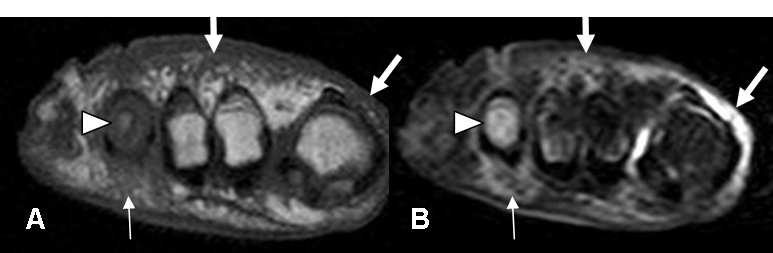

Fig 63. Pie diabético. Osteomielitis.

A: RM coronal en T1 y B: RM coronal en STIR. Osteomielitis del 4º metatarsiano hipointenso en T1 e hiperintenso en STIR (Punta de flecha), con cambios inflamatorios en los tejidos blandos. (Flechas delgadas). También hay cambios inflamatorios en el dorso del pie y sobre el 1º dedo. (Flechas gruesas).